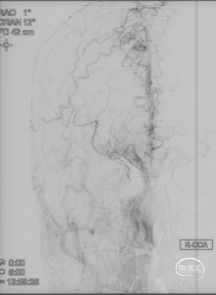

CTA和DSA

左右滑动查看更多

CTA和DSA所见:双侧颈内动脉闭塞,右侧椎动脉发出PICA后闭塞,左侧椎动脉V1-V2段闭塞。两条健壮的侧枝通过肌支吻合汇入左椎动脉V2段,构成了整个大脑大部分供血的主要来源。双侧颈外动脉亦有少量血流供应颅内。这样的颅内供血很容易发生失代偿,导致TIA甚至脑梗。